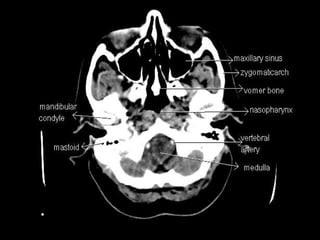

Radiographers use medical imaging equipment like X-rays and MRIs to produce images of patients' internal structures and organs. They are responsible for positioning patients, operating scanning machines, and ensuring quality images. Radiographers must have strong attention to detail, excellent communication skills, and the ability to work well under pressure to accurately capture anatomical features and diagnose any abnormalities.